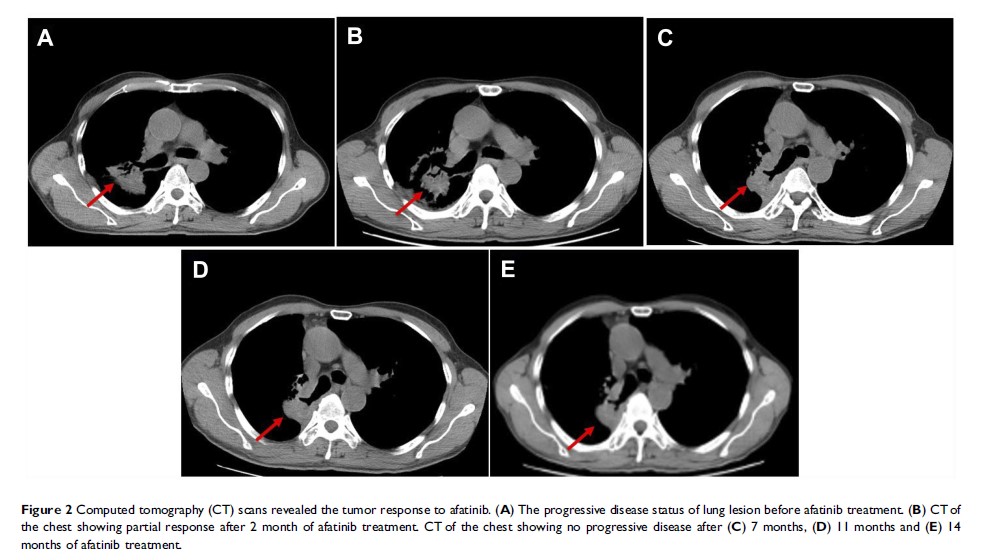

携带 HER2 R896G 突变的非小细胞肺癌患者对阿法替尼的反应:一份病例报告